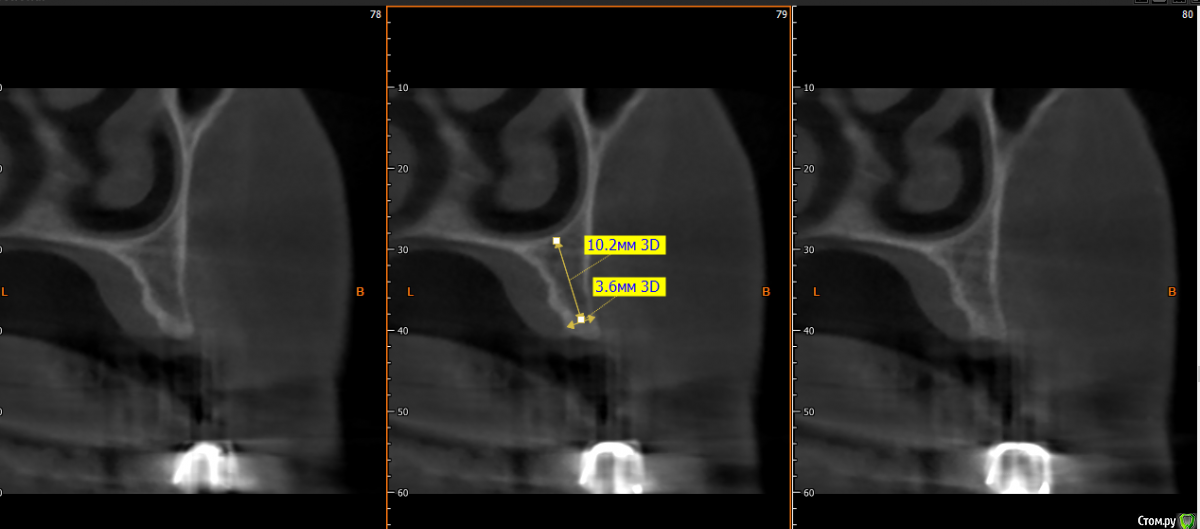

kramer Опубликовано 15 мая, 2019 Поделиться Опубликовано 15 мая, 2019 Коллеги, здравствуйте. Нужен совет. Ситуация: пациентка 70 лет (родственница), давно носила бюгельный протез, и вот одному из опорных зубов пришел конец. КТ ниже, фотографии завтра добавлю. Рассматриваю вариант изготовления несъемного протеза на 4 имплантатах. Опыта все-на-4 нет. Поэтому хотелось бы по крайней мере собрать информацию, возможна ли такая опция. Особенно волнует 2 момента: 1) Отсутствует вертикальная атрофия альвеолярного отростка во фронтальном отделе. Линия улыбки низкая. Предположим, окончательный протез будет м\к или циркон. Означает ли это, что редукцию кости делать необязательно? (правда там и редуцировать особо некуда). 2) В области 14 и 24 ширина гребня 3,5-4 мм. Что делать с этим? Оставлять пришеечную часть винта не покрытым костью небно или пытаться каким-то образом конденсировать кость? 14122224 Ссылка на комментарий

Smileee Опубликовано 16 мая, 2019 Поделиться Опубликовано 16 мая, 2019 Я бы везде установил 3.5, в области 24 немного редуцировал бы кость по вертикали. Все импланты максимально небно. Ссылка на комментарий